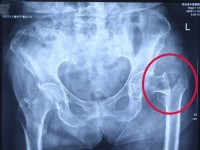

入院完善相关检查:骨盆平片清晰提示左股骨粗隆间骨折;左髋关节CT+三维重建进一步明确诊断为左股骨粗隆间粉碎性骨折(Evans-Jensen IB型),同时发现左髋关节退行性变及周围少量积液。结合老人既往病史及术前相关检查,中医诊断:骨折病(气滞血瘀证) ;西医诊断为:1. 左股骨粗隆间粉碎性骨折(Evans-Jensen IB型);2. 左髋关节骨关节炎;3. 慢性支气管炎伴感染;4. 多发性脑梗死;5. 冠状动脉粥样硬化性心脏病。